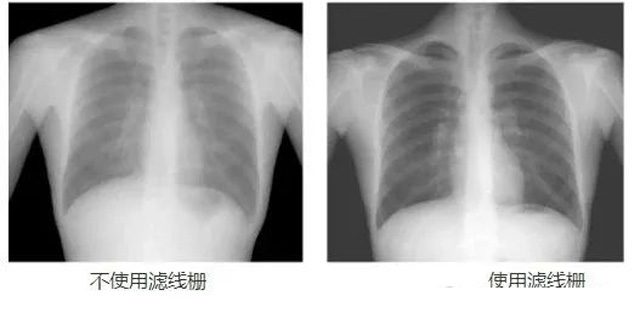

DR影像X射線在醫(yī)學(xué)檢查成像有著廣泛的使用。但是它的散射線影響成像質(zhì)量問(wèn)題。濾線柵的發(fā)明使用很好的解決了這個(gè)問(wèn)題,構(gòu)造簡(jiǎn)單鉛條粗,密度和柵比規(guī)格單一,能減散射線但吸收較多原發(fā)射線。伴隨這醫(yī)療影像設(shè)備技術(shù)的發(fā)展,這個(gè)濾線柵的工藝制造技術(shù)有改進(jìn),鉛條變薄,柵密度和柵比有更多的選擇。特別是材料方面有新組合,填充物也依不同成像要求優(yōu)化。特別是移動(dòng)DR這類(lèi)型的DR設(shè)備的出現(xiàn),濾線柵也設(shè)計(jì)成立方便拆卸形的,方便使用。被照體情況決定是否使用,更好平衡成像質(zhì)量與射線劑量。

放置方面:置于人體與片盒間,聚焦面朝向X線入射方向,X線焦點(diǎn)放鉛條會(huì)聚線上,不能反置,X線中心對(duì)準(zhǔn)濾線柵中心,左右偏移不超3cm,傾斜X線管要與鉛條排列方向平行。攝影時(shí)焦距改變不超焦距的25%;活動(dòng)式濾線器運(yùn)動(dòng)時(shí)間至少長(zhǎng)于曝光時(shí)間的1/5;因吸收原發(fā)射線要適當(dāng)增加曝光條件;四肢薄位置一般不用濾線柵;不同千伏對(duì)應(yīng)不同柵比;立位胸片架、乳腺DR攝影等有各自特定濾線柵要求。